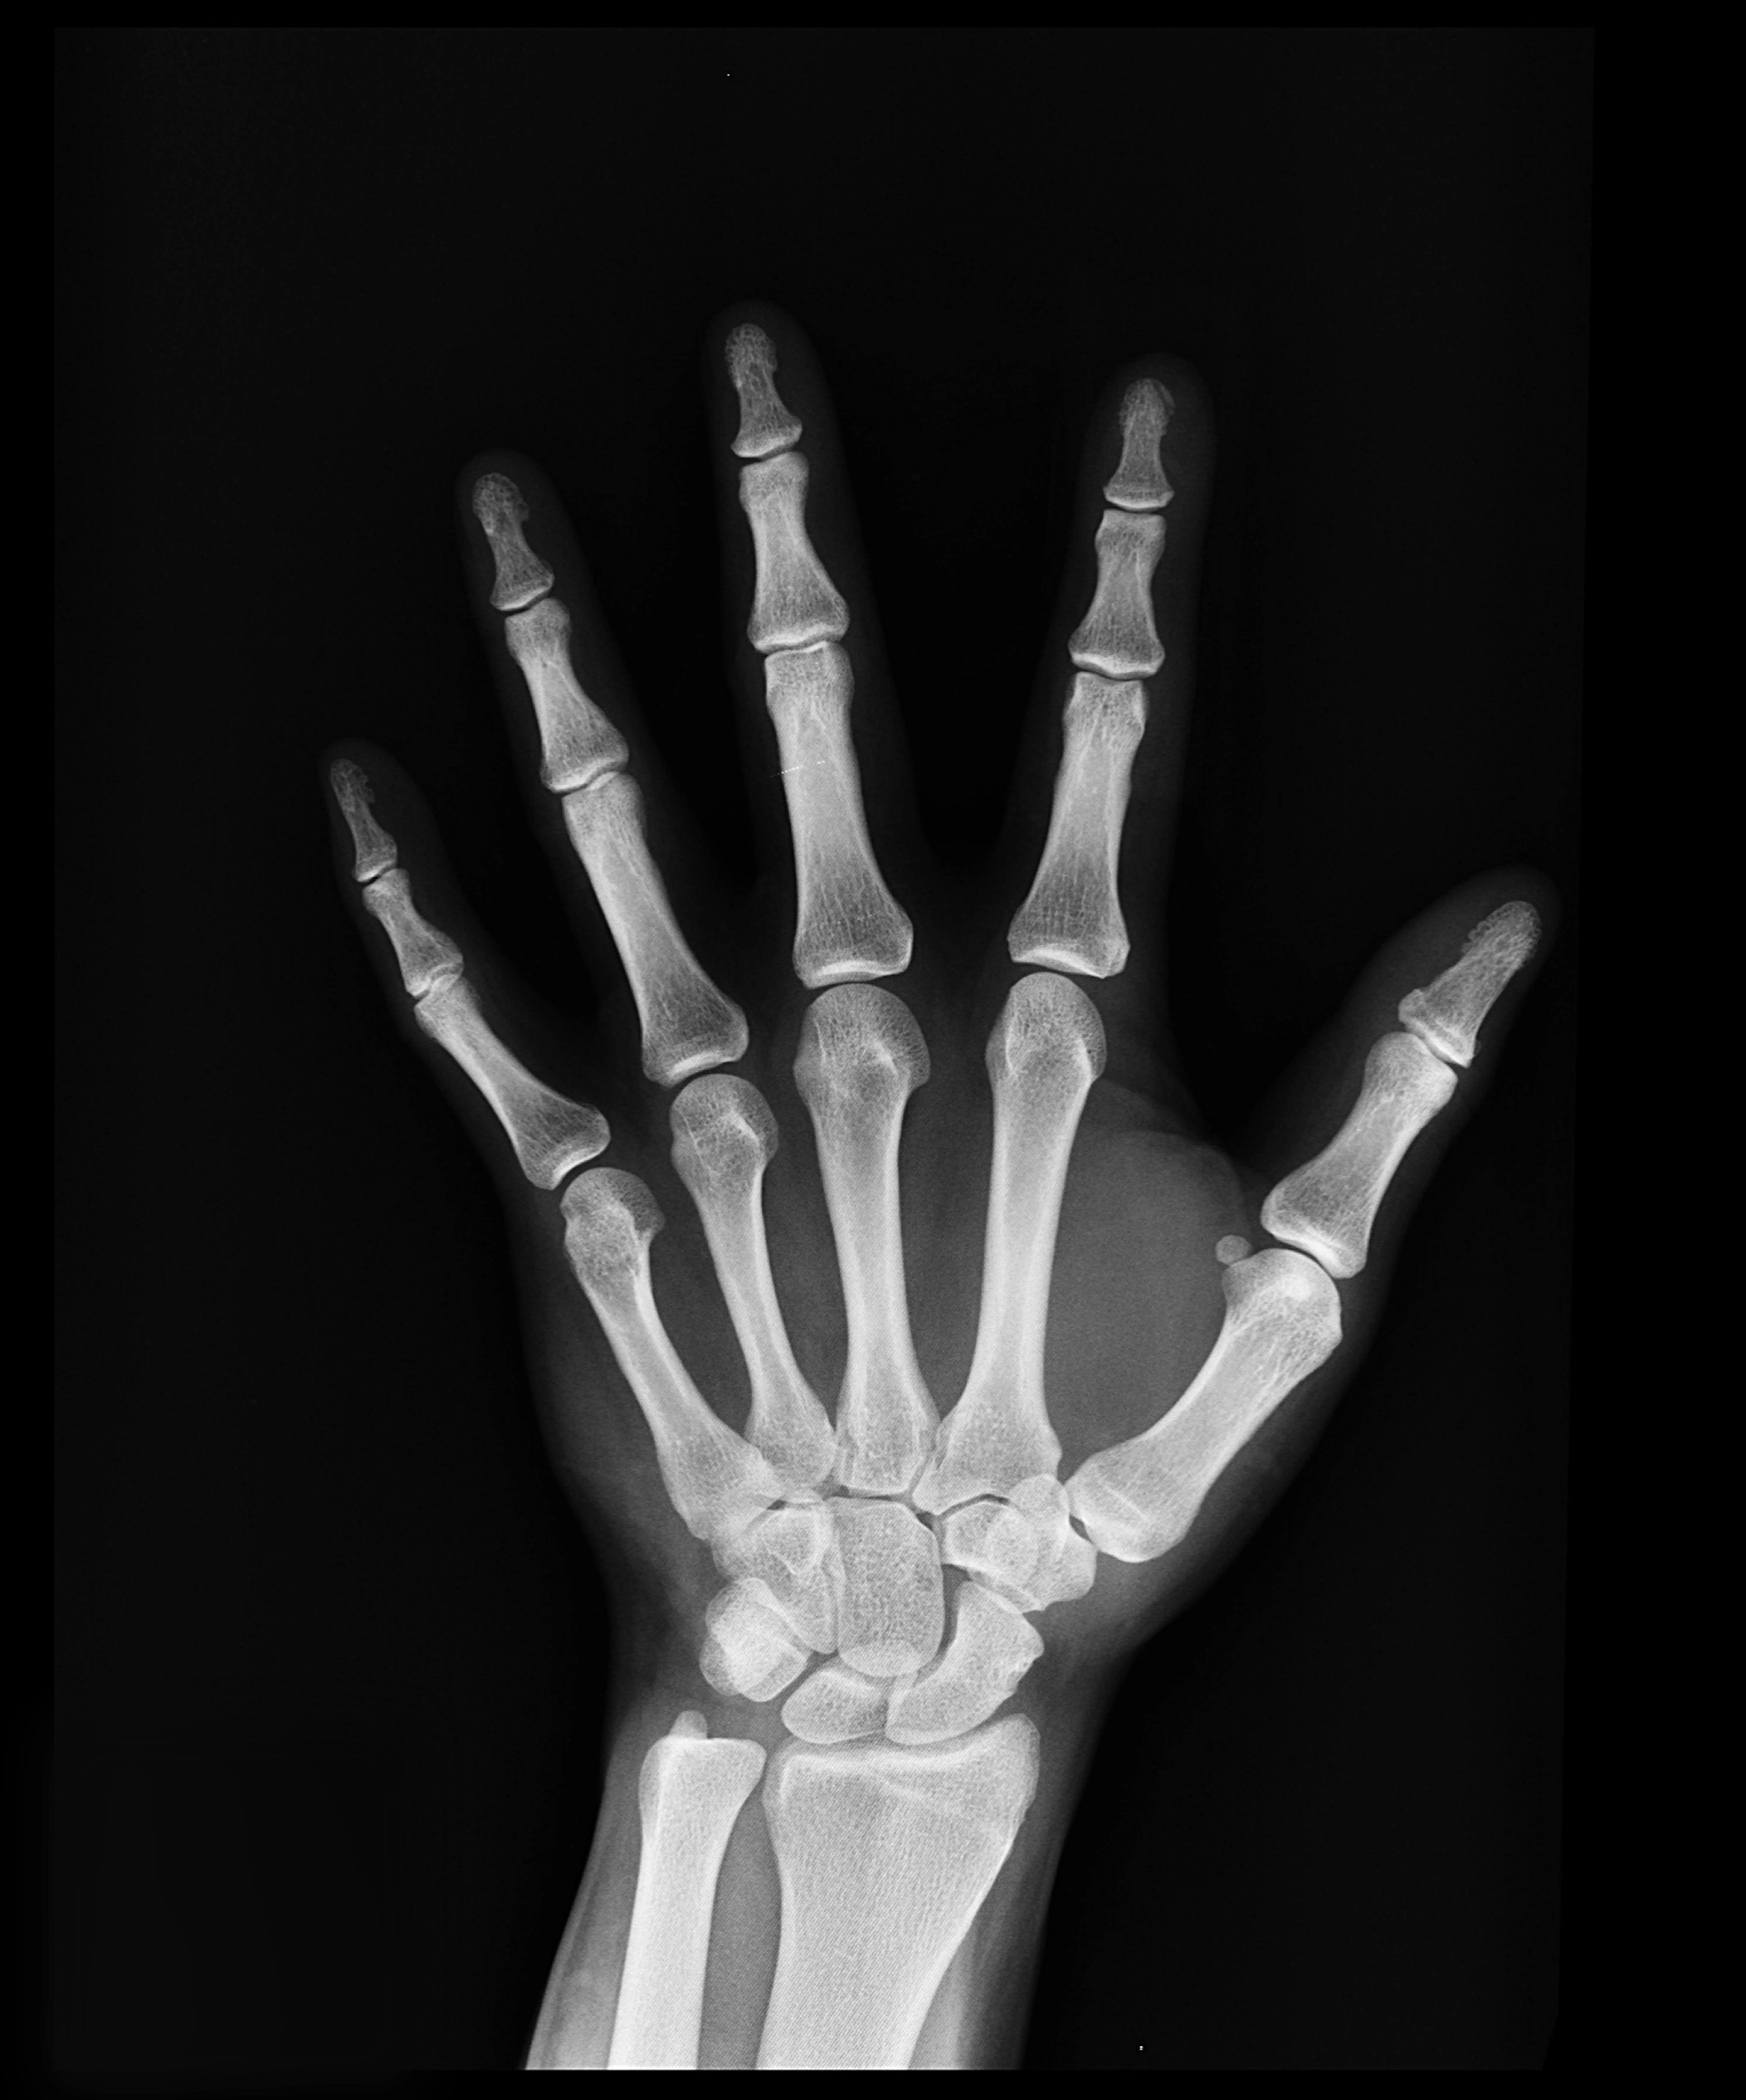

17. 17. X Rays Revealed Themselves During an Experiment

Pixabay on Pexels

X-rays began when physicist Wilhelm Roentgen experimented with cathode rays and noticed a glowing effect on a nearby screen. The glow appeared even though the screen was shielded. Roentgen investigated the phenomenon and discovered a new form of light that passed through solid objects. When he placed his hand in front of the screen, he saw the outline of his bones. This moment changed medical diagnostics because it allowed doctors to look inside the human body without surgery. The discovery soon spread across hospitals and research centers. Roentgen’s unexpected observation became one of the most important scientific advances. The moment demonstrated how curiosity and careful study can uncover entirely new forms of technology.